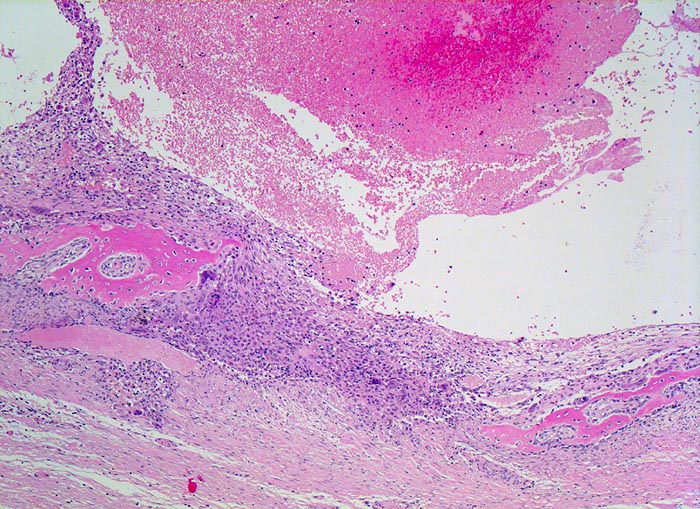

Die AKZ ist charakterisiert durch kavernöse Bluthohlräume mit dazwischengelegenen zellreichen Septen unter Einschluss von Riesenzellen. Da sekundäre AKZ häufig sind, muss das gesamte Material histologisch untersucht werden.

• Pseudozystische kavernöse Bluthohlräume eingebettet in Skelettmuskulatur.

• Die bindegewebigen Pseudozystenwände enthalten solide Massen von mononukleären histiozytenartigen Zellen mit eingestreuten mehrkernigen osteoklastären Riesenzellen.

• Neugebildeter reaktiver Faserknochen mit Osteoblastensaum in der Peripherie der Hohlräume.